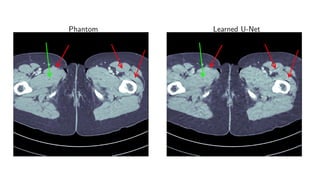

Results for ray transform inversion in 2D.

Compare to:

FBP

Total Variation

Post-processing deep learning by U-Net

Phantom Learned U-Net

Method PSNR (dB) SSIM Runtime (ms) Parameters

FBP 33.65 0.829 423 1

TV 37.48 0.946 64 371 1

Learned U-Net 41.92 0.941 463 107

Learned Primal-Dual 44.11 0.969 620 2.4 · 105